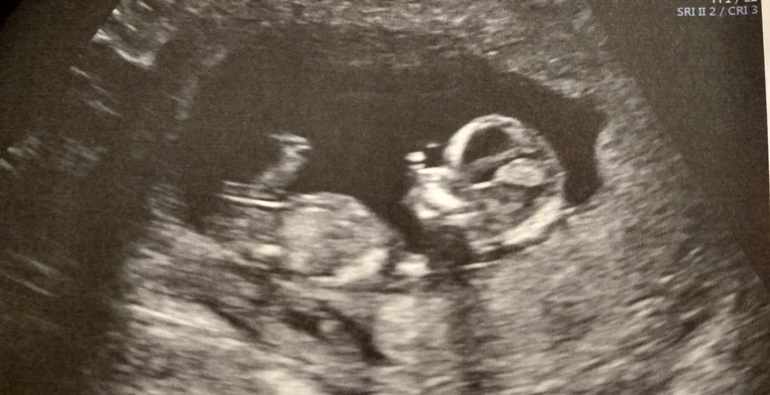

В ЖК была тётенька с суровым лицом, что я даже не посмела ничего спросить. Смотрели абдомиально (тут я удивилась). Мне сказали только срок (на 4 дня опережает срок по М) и что ничего плохого она не видит, а все результаты будут у врача. На несколько секунд повернула монитор, показала мне ребенка. Всё. Естественно меня это не устроило. Я подразумевала такой расклад, и заранее записалась к Пятых, ее мне советовали в прошлых постах, я почитала отзывы и ничуть не жалею потраченного времени и денег. Смотрели и через живот и вагинально. На отдельном мониторе я видела всё, мне показали все органы малышкА, пальчики, пяточки, сделали замеры параметров-маркеров ХА, все в норме. Здоровый ребенок с длинными ногами :) по сроку опять же на 4 дня больше чем по М. Включали ещё 3дэ. Ну и предположили девчонку. Я понимаю, что на таком сроке это 50/50, у кого -нибудь Пятых ошибалась на таком сроке с полом?